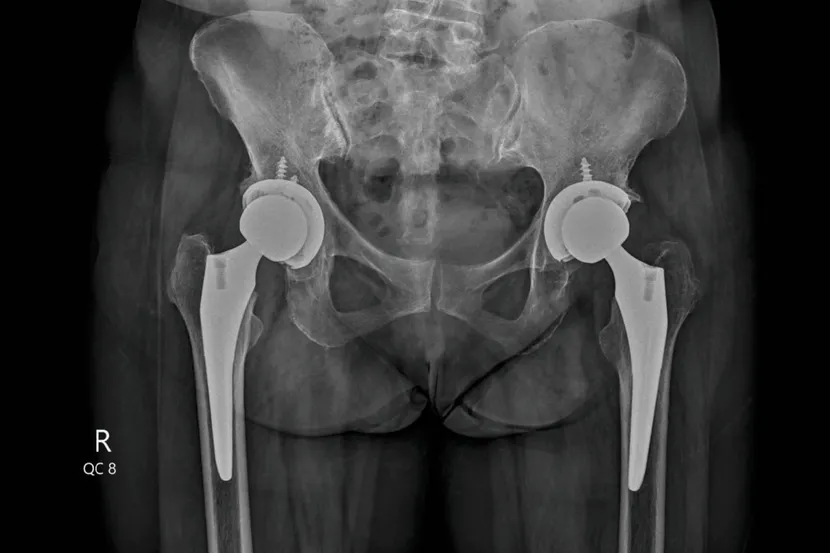

Totalna zamena kuka hirurška je procedura kojom se oštećeni zglob kuka menja veštačkim kukom (protezom), najčešće zbog artroze, osteoartritisa. Operacija kuka, koja uklanja bol i vraća pokretljivost, savetuje se kada konzervativne mere lečenja ne daju željene rezultate. Totalna zamena kuka ili totalna artroplastika kuka danas je jedna od najčešćih i najuspešnijih procedura za ublažavanje bola u kuku izazvanog artritisom ili drugim oštećenjima zgloba.

Lekari kažu da operacija kuka nije kao nekada rezervisana samo za starije osobe. U ranijim vremenima pacijenti su uglavnom bili stariji od 70 godina, dok se danas za ovu operaciju odlučuju i osobe u kasnim četrdesetim, pedesetim ili ranim šezdesetim godinama života. U isto vreme implantati su sve bolji i mogu da traju 25 godina ili i duže, objašnjavaju lekari.

Osobe koje imaju osteoartritis u jednom kuku imaju povećan rizik od razvoja osteoartritisa i u drugom kuku. Istraživanja pokazuju da oko 25 odsto pacijenata zameni i drugi kuk u roku od 10 godina.

Ranije su se ponekad oba kuka istovremeno operisala, ali se to danas ređe radi zbog većeg rizika kod nekih pacijenata.

- Ipak, istovremena operacija oba kuka ima i svoje prednosti: pacijent dobija samo jednu anesteziju, a odsustvo sa posla je kraće. Kod mlađih i zdravijih pacijenata neki hirurzi i dalje nude ovu opciju - zaključuje dr Mansur.